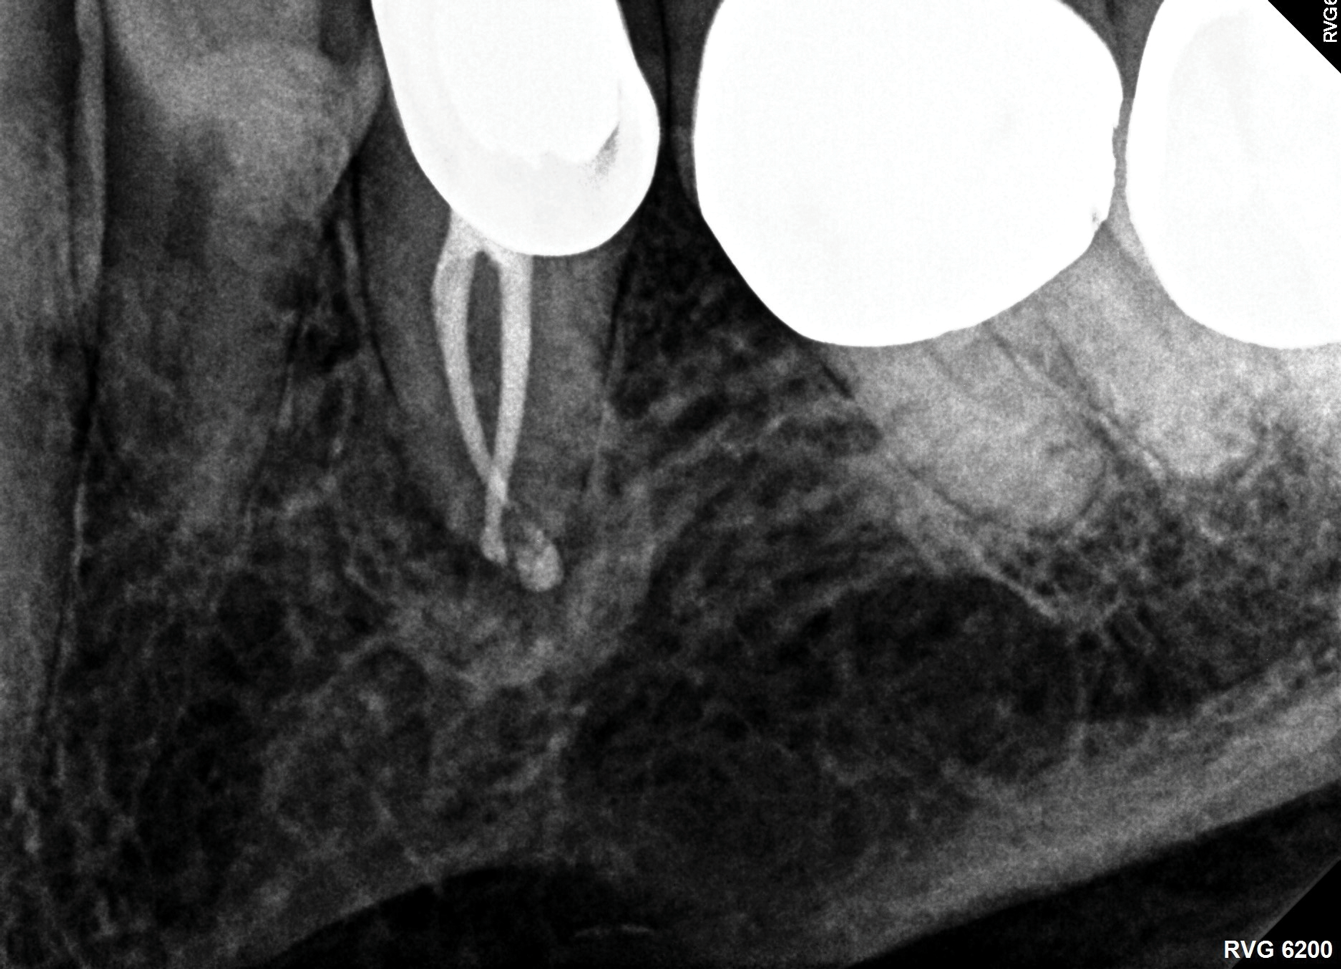

Fig 6. Identifiable inadequate NSRCT is associated with predictable RETX. Fig 6: Preoperative periapical radiograph showing AP, tooth No. 20. Fig 7. Postoperative periapical radiograph. Fig 8. Six-month follow-up periapical radiograph showing a significant decrease in size of the AP.

Figure 6

Fig 8. Identifiable inadequate NSRCT is associated with predictable RETX. Fig 6: Preoperative periapical radiograph showing AP, tooth No. 20. Fig 7. Postoperative periapical radiograph. Fig 8. Six-month follow-up periapical radiograph showing a significant decrease in size of the AP.

Figure 8

The quality of the initial NSRCT is inversely associated with RETX outcomes, with poorer quality initial treatment tied to more predictable retreatment (Figure 6 through Figure 8).23 Inadequate quality of the initial NSRCT (eg, untreated anatomy, under-instrumentation, ledged and underfilled canals, and overextended obturation) was associated with greater predictability following RETX. However, if clinicians cannot identify and correct the mistakes made in the previous root canal therapy, it becomes more challenging to improve treatment outcomes.23